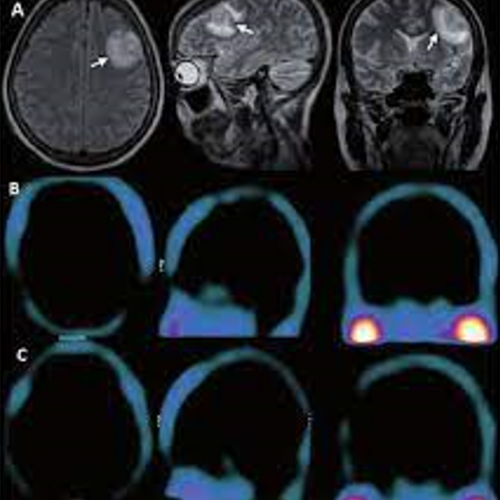

GAMMAGRAFÍA CEREBRAL CON MIBI

Identificación de lesiones tumorales o metastásicas en tejido cerebral.